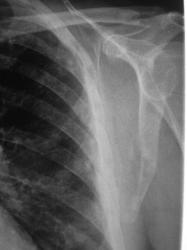

Иллюстрации 3. 4. Слева в области латерального латерального края лопатки, в ребрах определяются участки остеопоротической перестройки структуры костной ткани — литический вариант.

Иллюстрации 5, 6. Справа аналогичные изменения в ребрах и лопатке.